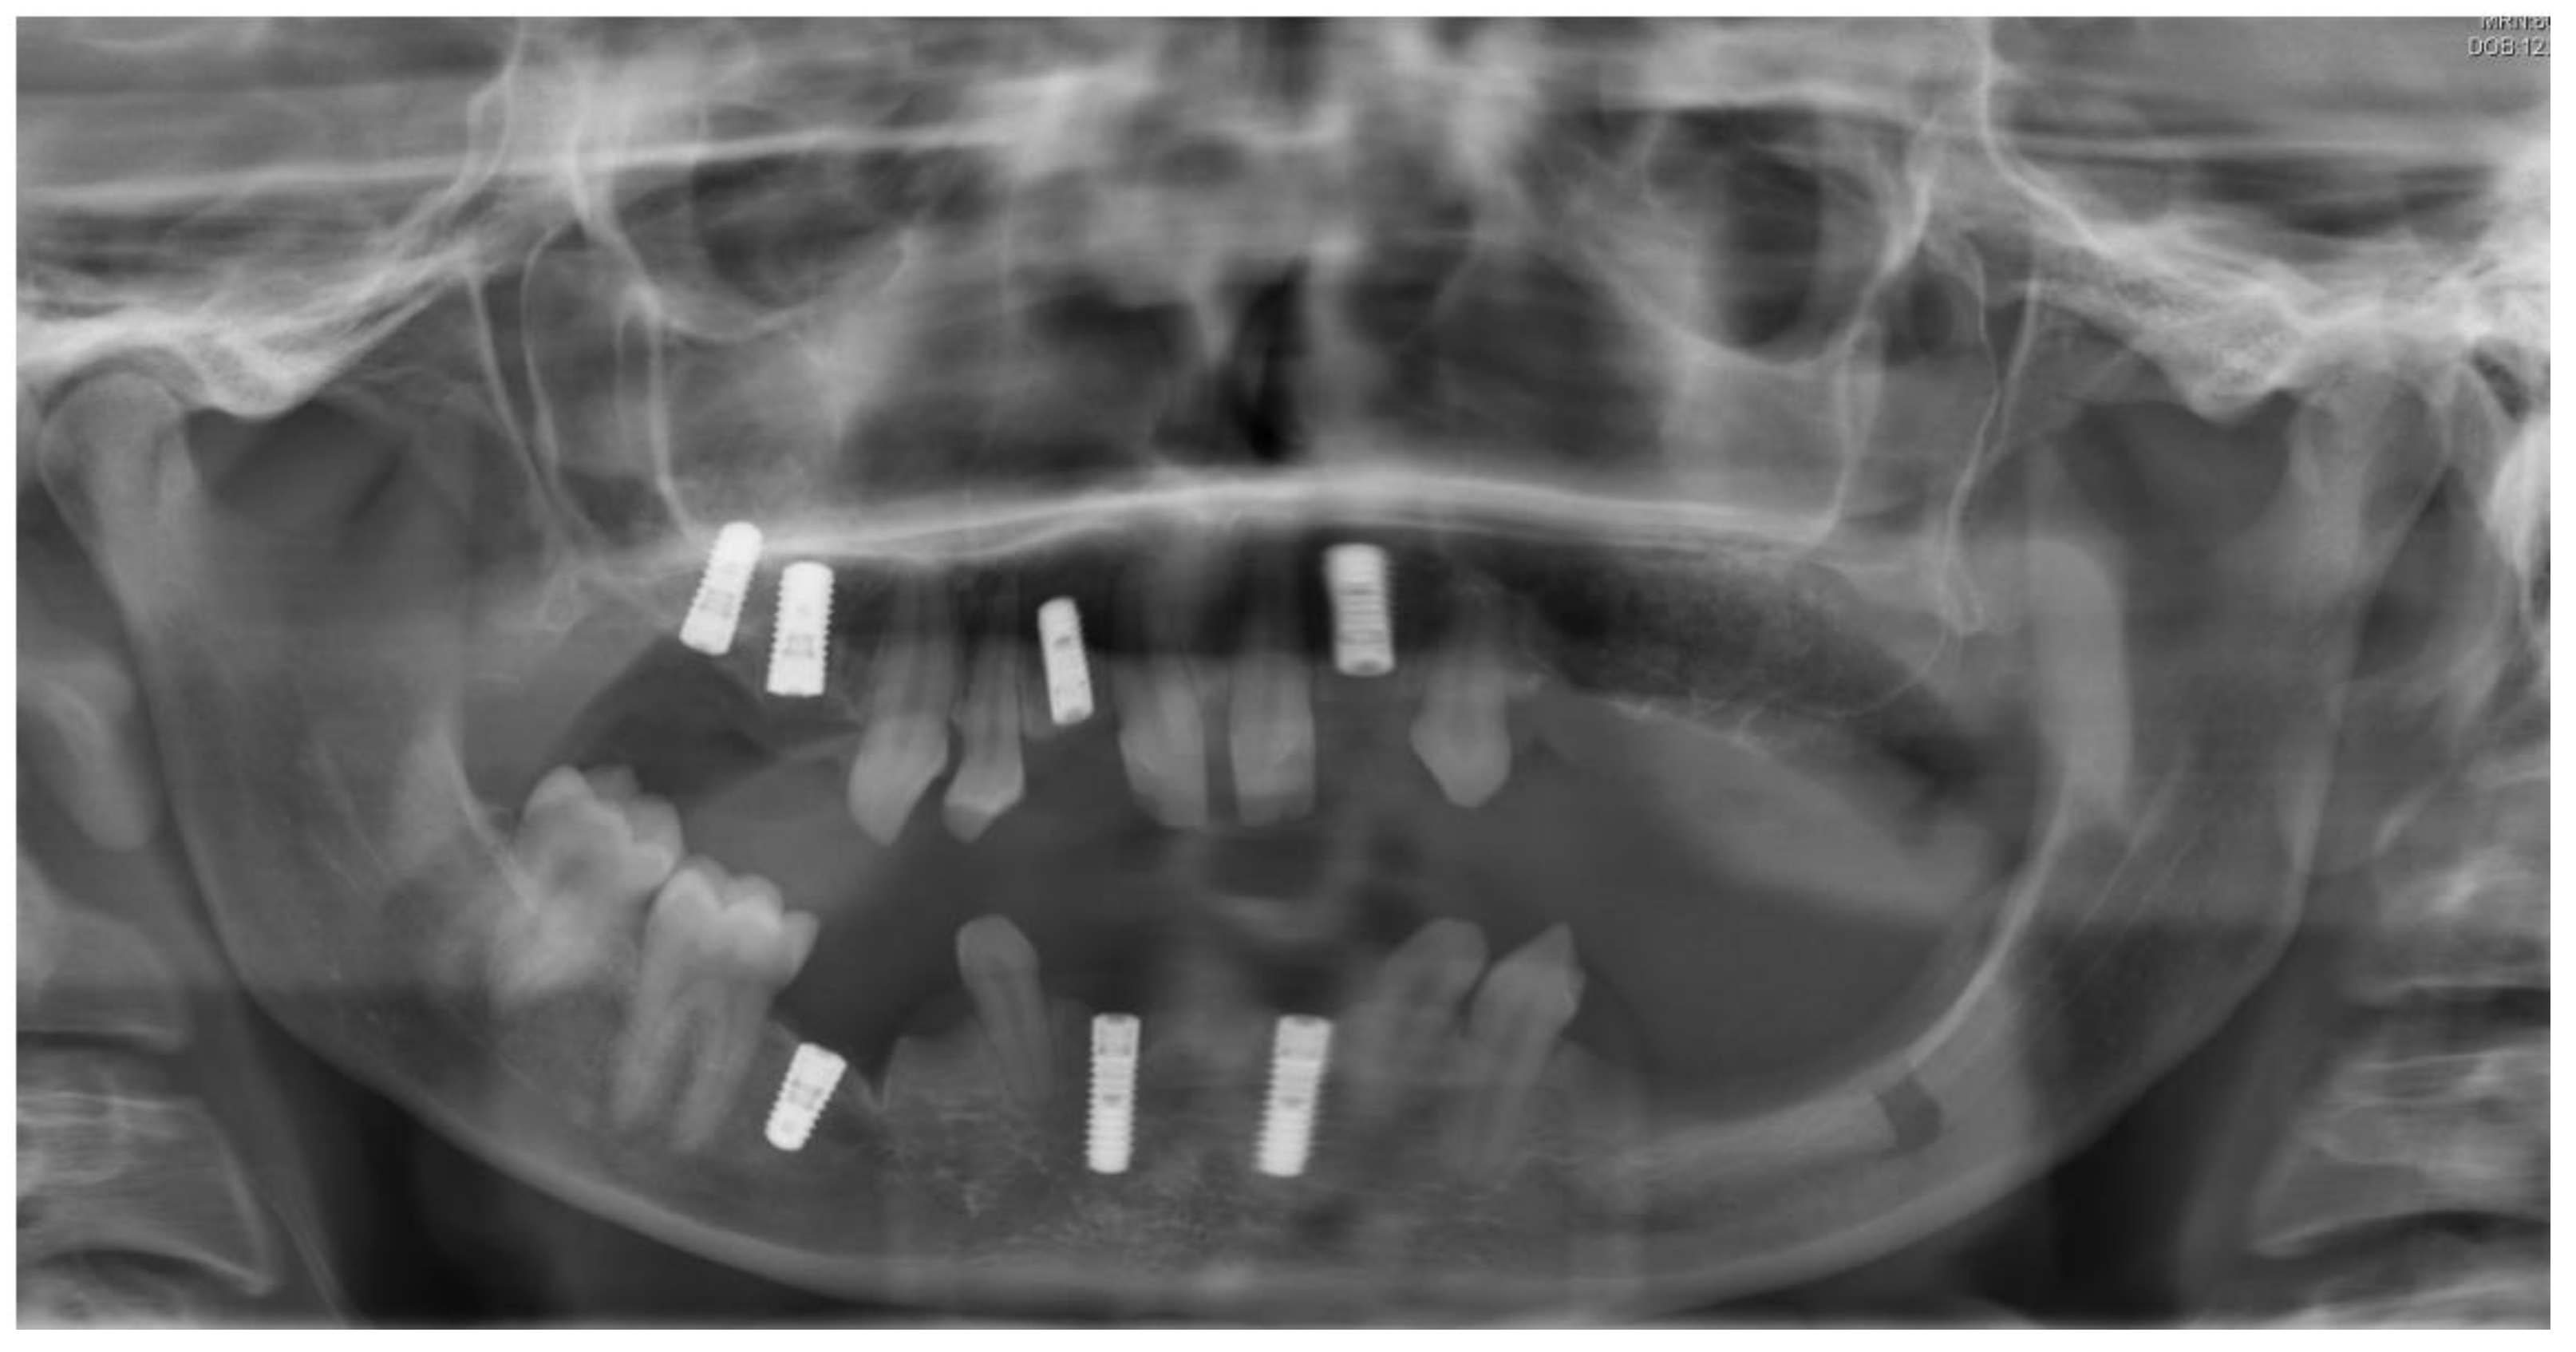

2.1. Case One